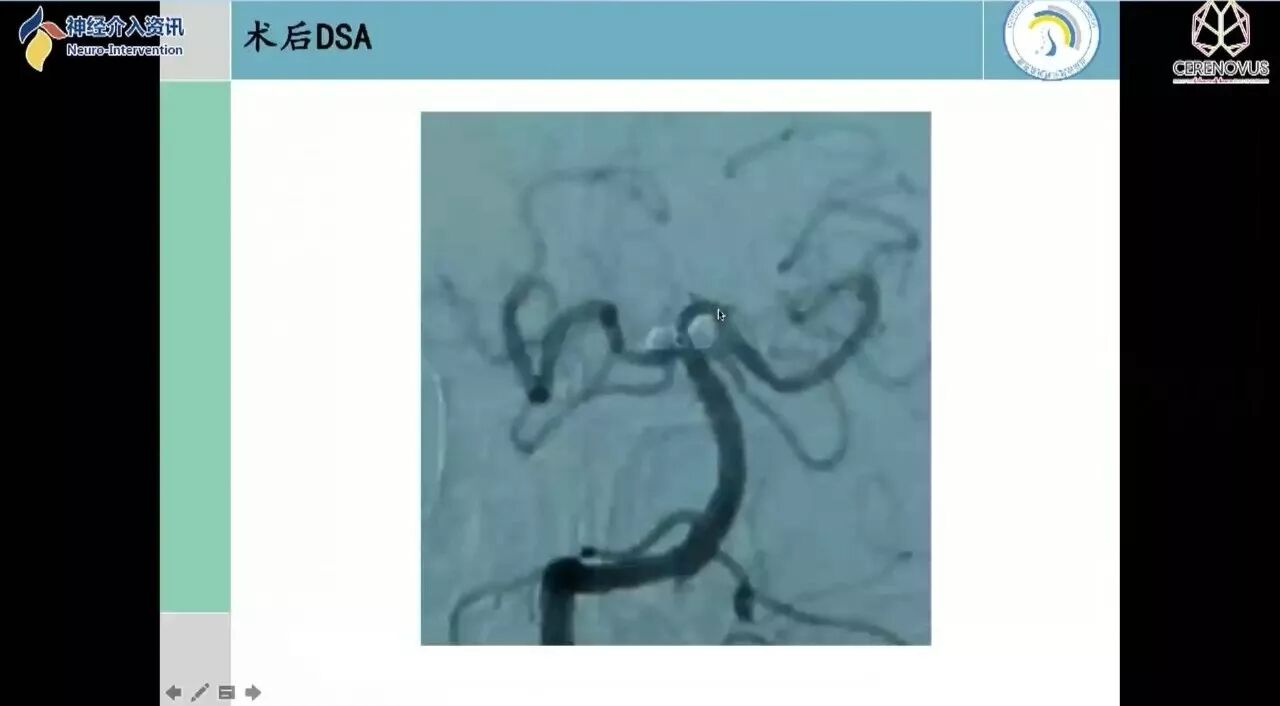

Galaxy弹簧圈在小动脉瘤栓塞术中的应用